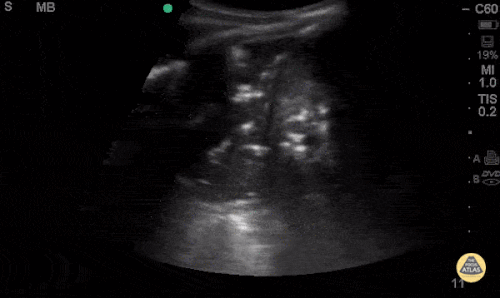

Question 2: This 65-year-old woman presents with dyspnea and fever. She presented to her doctor a week ago with fever and cough, for which she was treated with azithromycin. She was feeling better for a while, but has been declining for the past couple days.

- Describe the ultrasonographic findings.

- What is your differential diagnosis for this ultrasound pattern?

- What is your diagnostic and therapeutic plan for this patient?